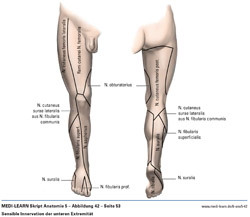

• Sensible Innervation der unteren Extremität